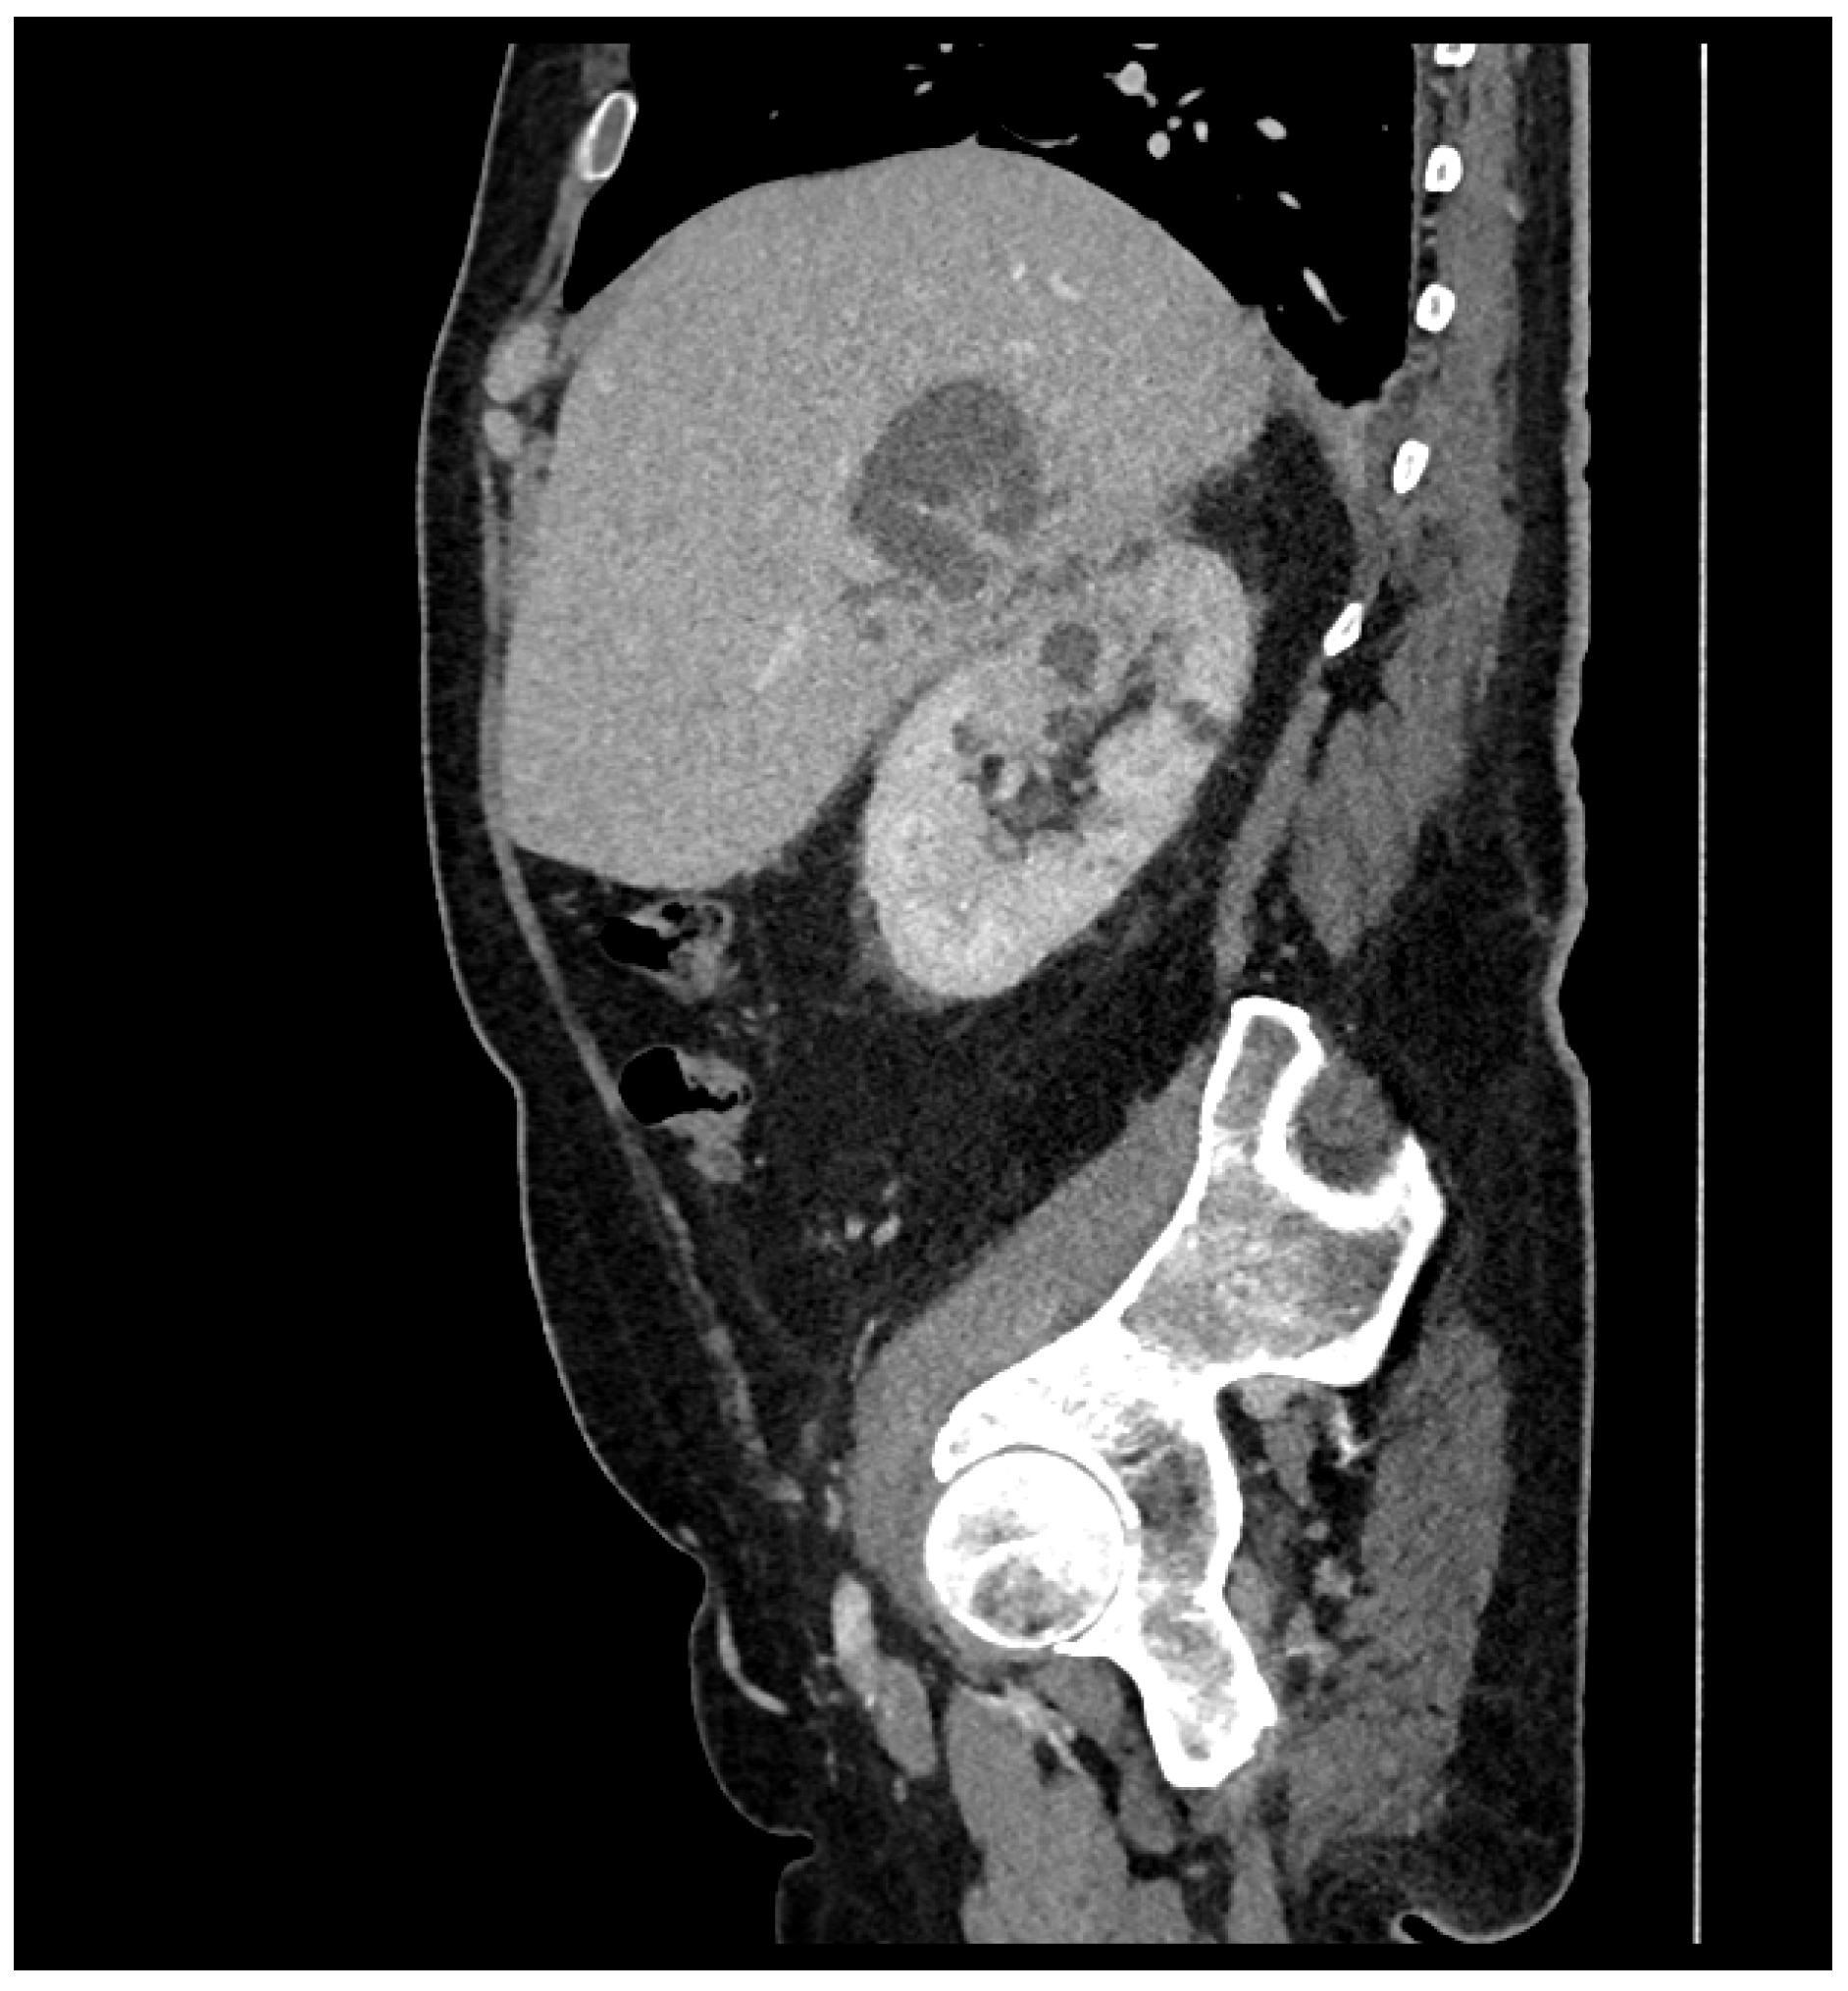

2. Case Report